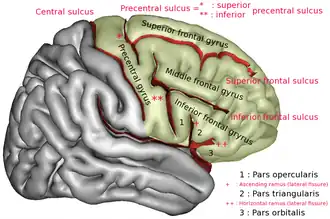

Lateral surface of right frontal lobe. Precentral sulcus is labeled by * and **.

Lateral surface of right frontal lobe. Precentral sulcus is labeled by * and **. -